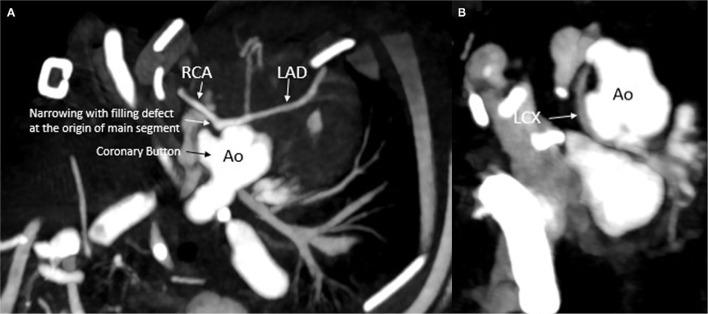

病例报告:大动脉转位合并新型冠状动脉解剖结构的新生儿围手术期决策挑战

Case Report: Challenging Perioperative Decision-Making in a Neonate With Transposition of Great Arteries and Novel Coronary Anatomy.

Transposition of great arteries (d-TGA) is often associated with various coronary artery (CA) patterns. These anomalous patterns can cause variable clinical symptoms of coronary ischemia including sudden death. CA pattern is one of the major determinants of outcome in TGA postoperatively. An advanced cardiac imaging and a multidisciplinary care approach are essential for a favorable outcome. Here, we describe a novel CA origin pattern in a neonate with d-TGA, who developed myocardial ischemia and required a coronary unroofing procedure for a full recovery.

摘要

大动脉转位(d-TGA)常与多种冠状动脉(CA)形态相关。这些异常形态可导致包括猝死在内的冠状动脉缺血的不同临床症状。CA形态是d-TGA术后预后的主要决定因素之一。先进的心脏成像和多学科护理方法对于取得良好预后至关重要。在此,我们描述了一名患有d-TGA的新生儿中一种新的CA起源形态,该患儿发生了心肌缺血,需要进行冠状动脉开窗术才能完全康复。